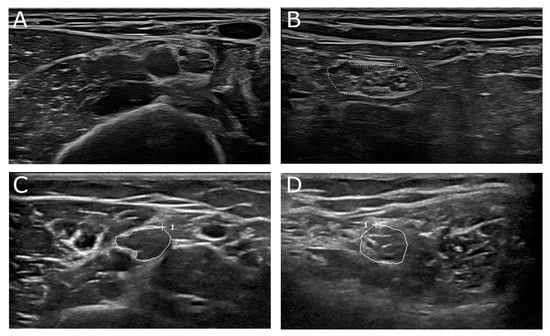

- Winter, N.; Dammeier, N.; Schäffer, E.; Bornemann, A.; Stahl, J.H.; Herlan, S.; Schuhmann, M.U.; Grimm, A. Nerve Ultrasonography as an Additive Tool to Clinical Examination and Electrodiagnostics in Sporadic Mononeuritis-Imaging is the Key. Ultraschall Med. 2019, 40, 465–472. [Google Scholar] [CrossRef] [PubMed]